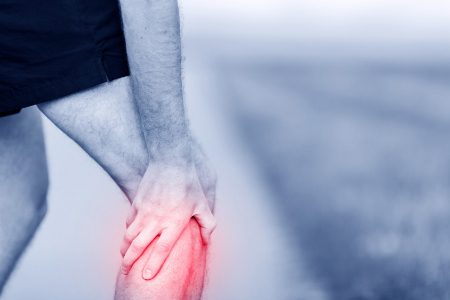

اسب چارلی در کمین پاها: علائم و درمان گرفتگی عضلات

عبارت «اسب چارلی» اصطلاحی رایج برای گرفتگی ناگهانی و غیرارادی عضلات، به خصوص در پاها است. این گرفتگی میتواند در هر ماهیچهای از بدن رخ دهد، اما بیشتر در پا اتفاق میافتد. احتمال اینکه در هنگام خواب یا ورزش دچار اسب چارلی شوید، بیشتر است.

• اسب چارلی باعث ایجاد درد ناگهانی و شدید در عضله میشود.

• احساس سفتی شدید در عضله خواهید کرد، انگار که گره خورده باشد. حتی ممکن است هنگام لمس، عضله سفت به نظر برسد.

• گاهی اوقات، ممکن است عضله آسیب دیده دچار تغییر شکل شود یا حتی ببینید که میجهد.

• گرفتگی اغلب عضلات پا را تحت تاثیر قرار می دهد، به ویژه ساق پا.

اسب چارلی یک اسپاسم یا گرفتگی ناگهانی، دردناک و غیرارادی عضلانی است. در حالی که معمولاً در پای شما، به ویژه ساق پا رخ می دهد، می توانید در هر عضله ای به آن مبتلا شوید. اسب چارلی می تواند در هر زمانی از روز رشد کند، اما بیشتر با حضور در رختخواب و ورزش مرتبط است. اغلب زمانی اتفاق می افتد که عضله شما بیش از حد کار کند یا آسیب دیده باشد یا اگر بدنتان کم آب باشد.